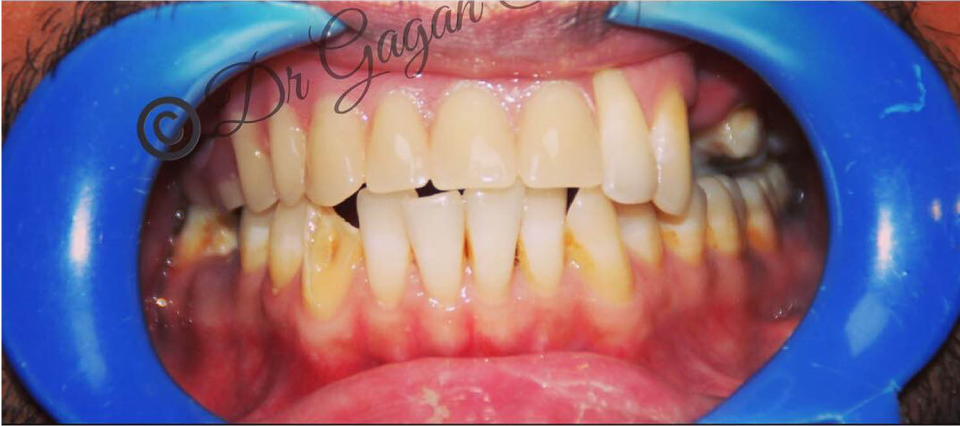

Complex Implant Rehabilitation

Complex dental implant rehabilitation is a highly effective solution for patients with extensive dental issues.

Such as severe bone loss, multiple missing teeth, cases involving tumor resection and reconstruction with vasculised bone grafts, gun shot injuries, with cleft lip and palate, jaw necrosis, post cancer oral rehabilitation.

Treatment plan includes Detailed clinical and radiographic evaluation of the patient’s general and oral health, including gum condition, remaining teeth, and bone structure with 3D scans, X-rays, and CT scans.

Benefits of Complex Dental Implant Rehabilitation:

- Restores form and Functionality

- Improves quality of life

- Improved Aesthetics

- Bring back lost confidence